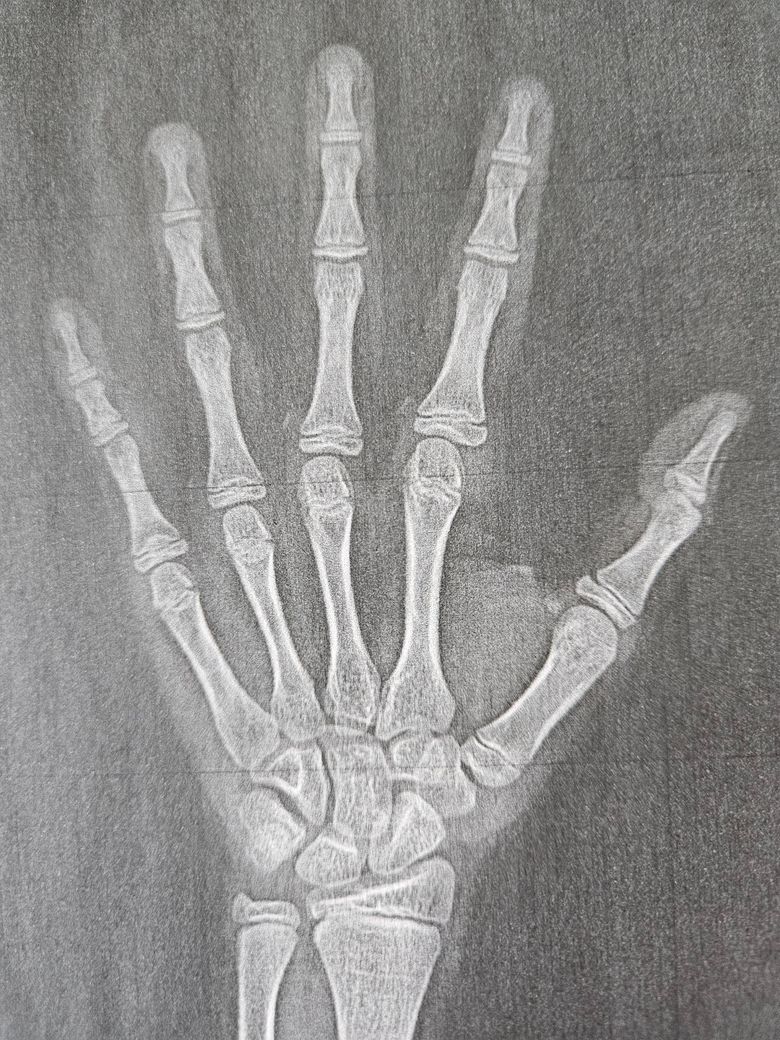

성장판검사 사진인데 예상나이 예측부탁합니다

성장판 검사한 후 프린트 된 아이 왼손 엑스레이 사진입니다 두병원에서 좀 차이가 나는데 예측나이 좀 판독해 주셔요. 키 성장에 도움되는 영양소도 궁금합니다

수완부 방사선 사진 상 중지의 원위지골 골단의 모양을 보고 연령을 파악하는데요. 지금 보면 FG~G 단계로 11세~13세로 보입니다. 최대 성장기 즈음인 것 같습니다.

키 성장과 관련해서는 종합비타민제 도움이 될 수 있으나 절대적인 영향을 미치진 않습니다.

키성장에는 칼슘, 비타민디, 아연이 도움이 됩니다.